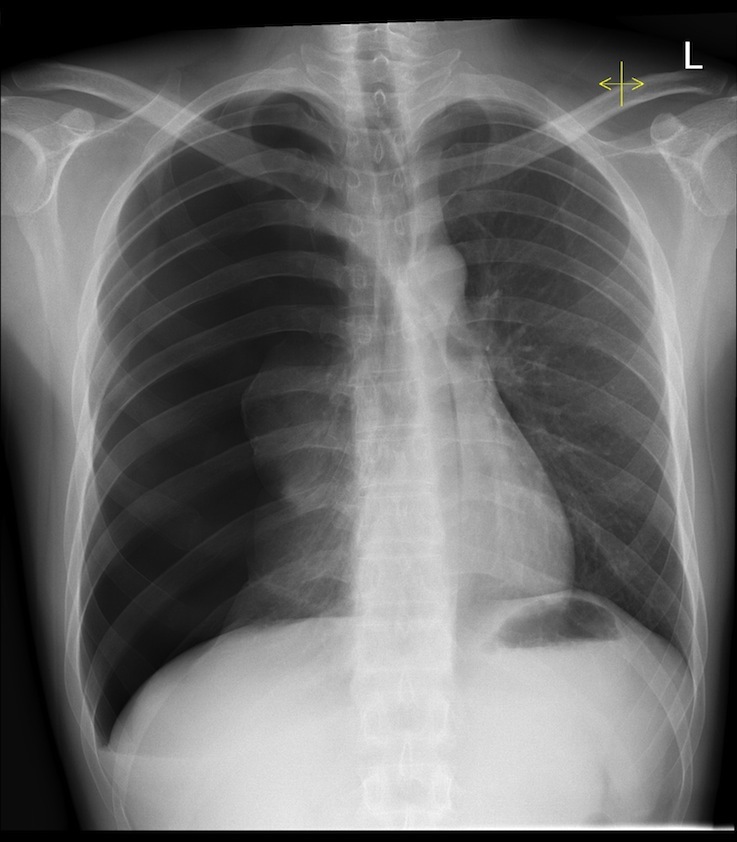

Describe the abnormality/ies

Tension pneumothorax

(with tracheal deviation)